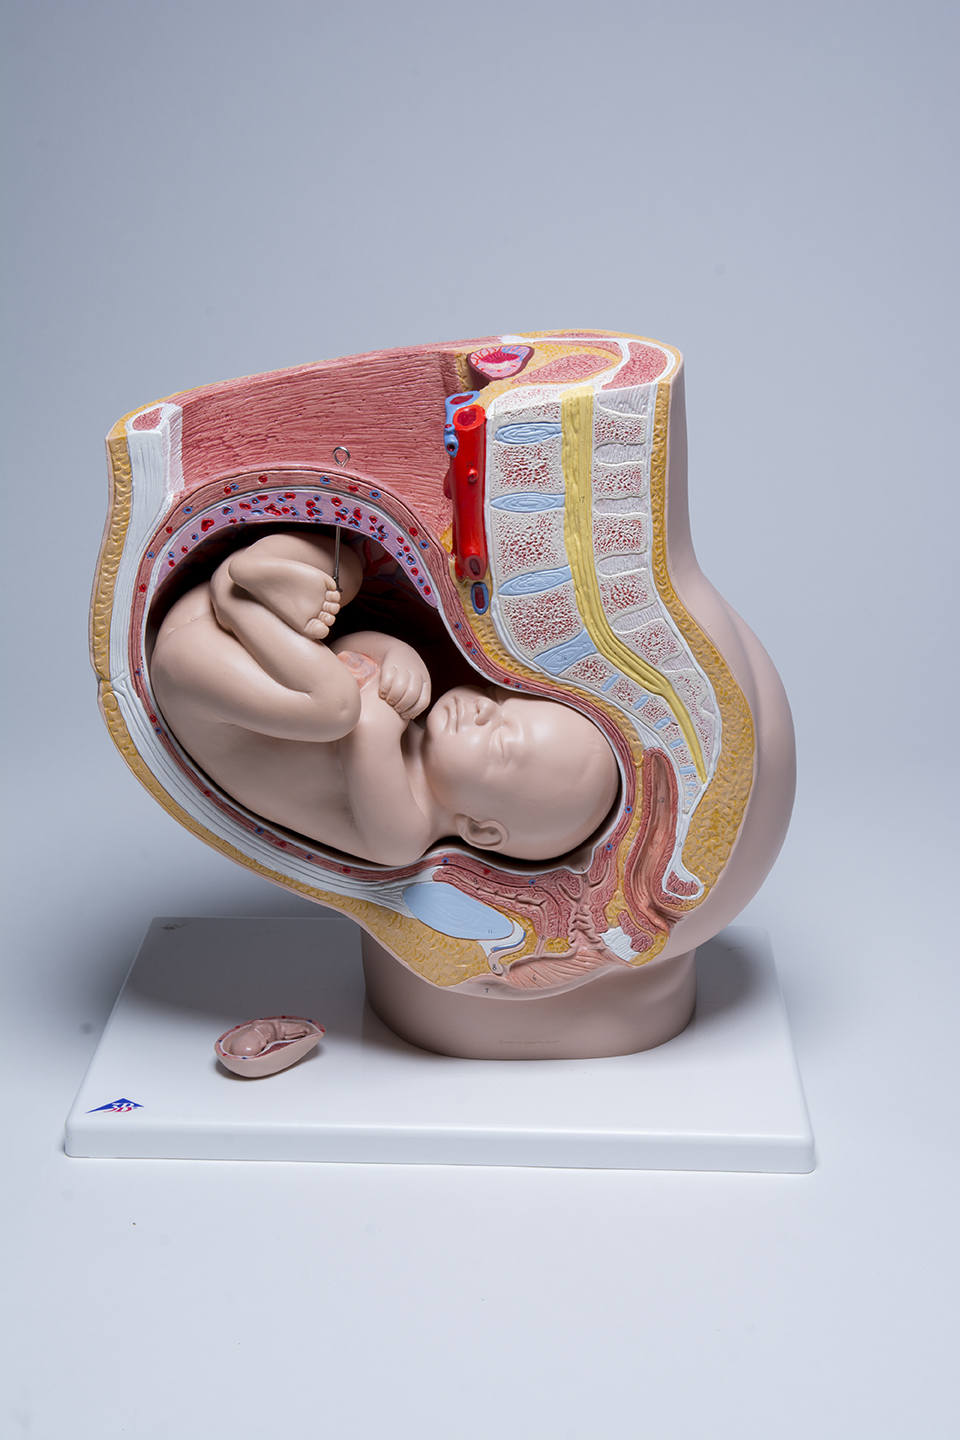

Pelvic Anatomy Pregnancy Model

This anatomy pregnancy model is a representation of a median section through the female pelvis at 40 weeks pregnant with a removable fetus. Study the normal position of child before birth with this model plus the human reproductive and urinary systems. A uterus with embryo in 3rd month of pregnancy is mounted on base for added detail. The realistic and high quality female pelvis includes the female genital organs and other important anatomical details. This pregnancy female pelvis is a great addition to any anatomy classroom or clinician’s office to educate about the effects of pregnancy.

This pelvic anatomy pregnancy model allows the clinician to easily explain what is taking place internally during pregnancy and how it affects surrounding organs, muscle and bone. This will enable to clinician to point out the many issues that can arise from childbirth and what can be done proactively to prevent them.